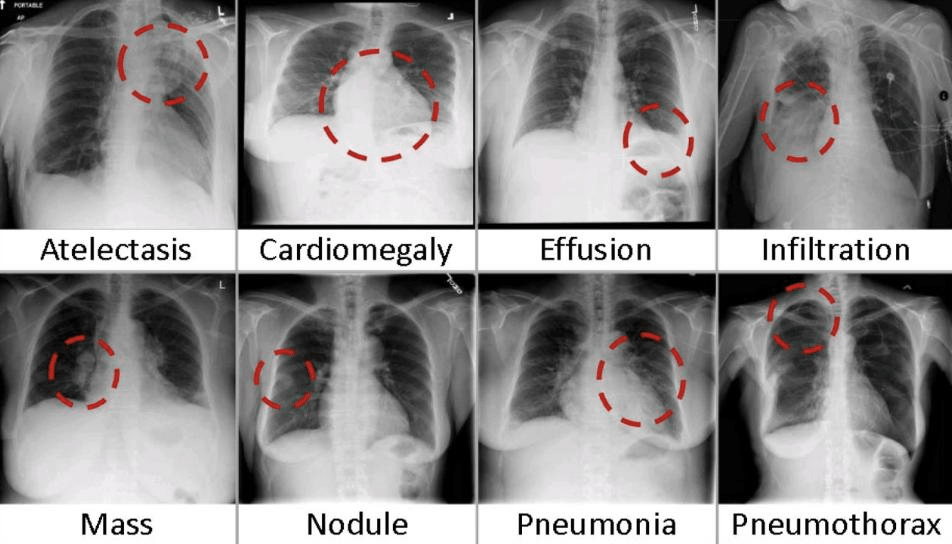

Era of Open Data

• 30, 000+ patients

• 10,000 + images

• Each associated with 14 labels

• Derived automatically from free-text reports

• Freely, publicly available

NIH Dataset